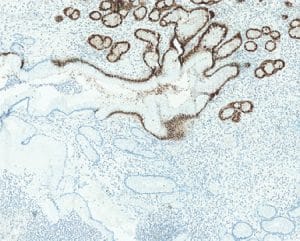

From the chapter “Genetic tumour syndromes of the digestive system,” juvenile polyposis syndrome.